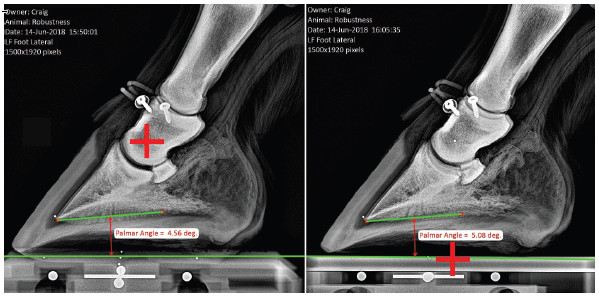

Learn how to take quality radiographs and photographs of the horse's hoof for precise measurements

Utilize Metron software for easy and precise measurements

Join Dr. John Craig, PhD in this exclusive course to master the art of equine hoof imaging. Learn the techniques to capture accurate images and make measurements, in particular, using the revolutionary 'Metron Block'. Enhance your skills and achieve precision in equine hoof analysis. Even practicing equine veterinarians will learn something new in this webinar! Enroll now to elevate your imaging capabilities!